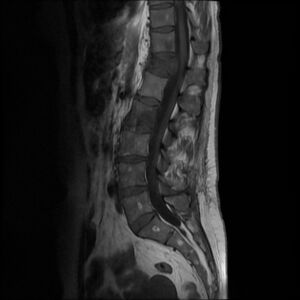

- MR – primary choice, especially axial and sagittal T1 and T2 images. In practice, DTI (diffusion tensor imaging) and FT (fiber tractography) are already commonly used for more detailed imaging of white matter pathways (their displacements, compression, etc.) due to tumor location. [5][6][7].

Extradural tumors represent the majority of spinal tumors (55%)[4]. These are mostly secondary tumors.

Secondary tumors of the spinal cord are caused by metastases of cancers from various areas of the body. The most common cancers are lung, breast, prostate, kidney, thyroid [2][3]. Extradural metastases represent about all 95% of spinal metastases [27].

The most frequently affected area of extraspinal metastases is the thoracic and lumbar segment of the spine - the cervical area is minimally affected [2].